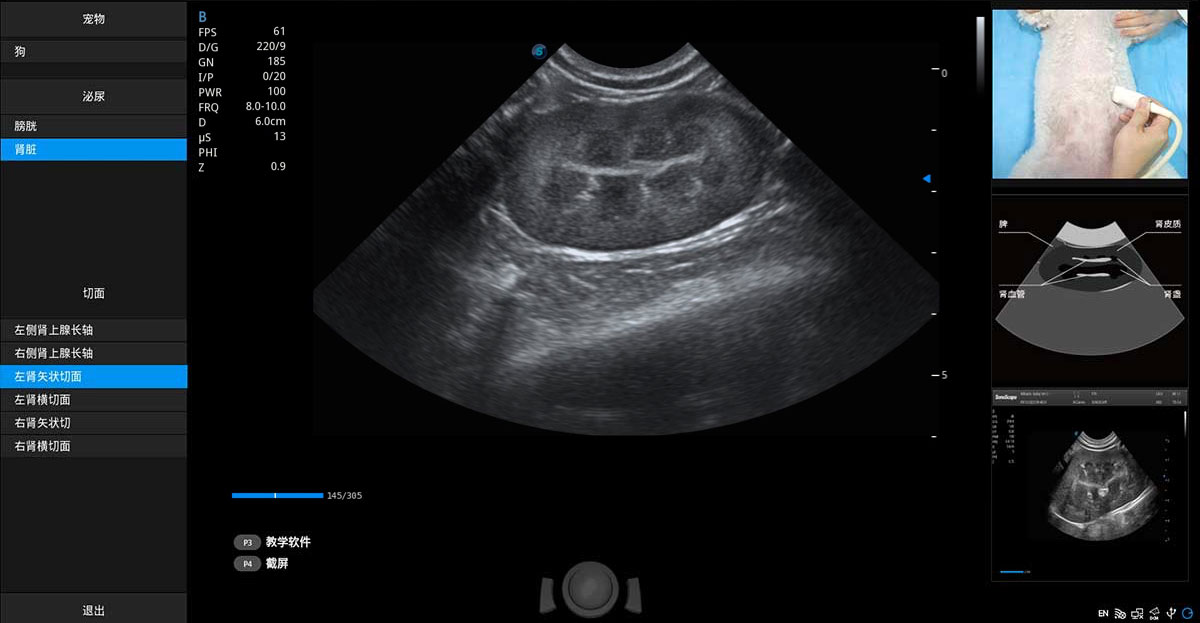

提供解剖示意圖、標(biāo)準(zhǔn)超聲圖像、掃查手法圖和操作者實(shí)時(shí)檢查圖像,指導(dǎo)操作者進(jìn)行標(biāo)準(zhǔn)切面的正確掃查。

ProPet 70專為動(dòng)物醫(yī)生設(shè)計(jì),對不同的動(dòng)物體型和生理結(jié)構(gòu)作出了針對性的優(yōu)化。通過動(dòng)物影像專用軟件,可滿足個(gè)性化的應(yīng)用需求,幫助動(dòng)物醫(yī)生獲得更精確的診斷數(shù)據(jù)。